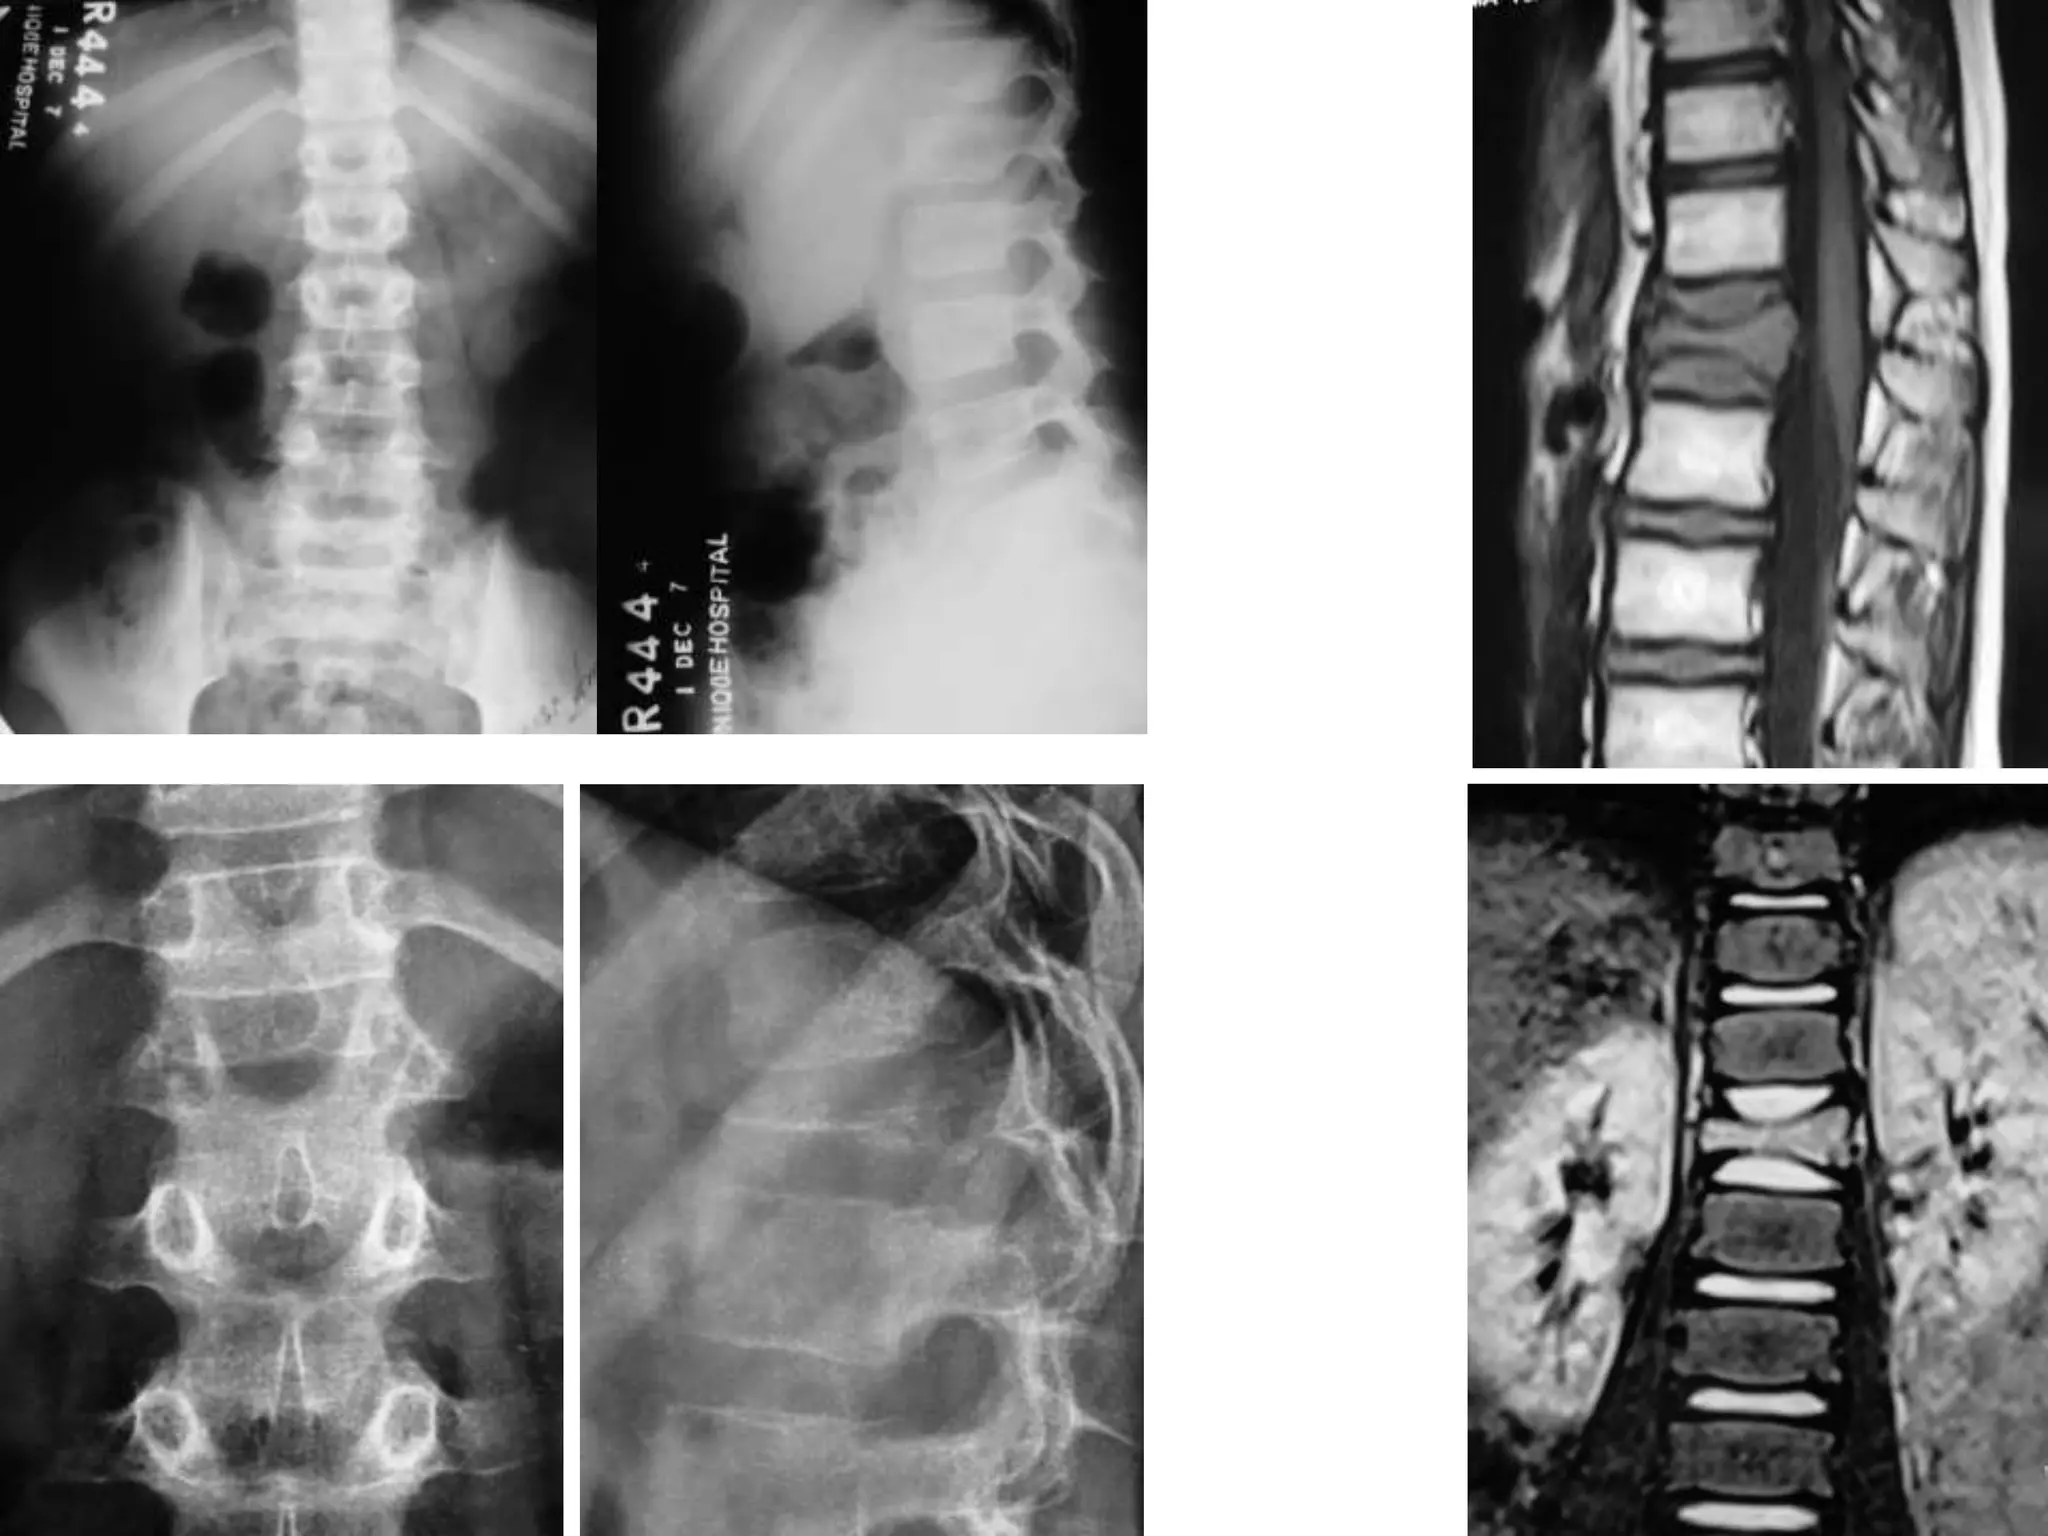

Epidural Abscess

Aneurismal Bone Cyst

Heamengioma